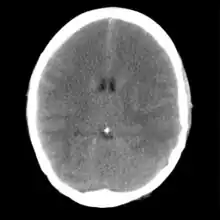

Brain

.jpeg.webp)

Brain ischemia is insufficient blood flow to the brain, and can be acute or chronic. Acute ischemic stroke is a neurologic emergency that may be reversible if treated rapidly. Chronic ischemia of the brain may result in a form of dementia called vascular dementia.[8] A brief episode of ischemia affecting the brain is called a transient ischemic attack (TIA), often called a mini-stroke. 10% of TIAs will develop into a stroke within 90 days, half of which will occur in the first two days following the TIA.[9]